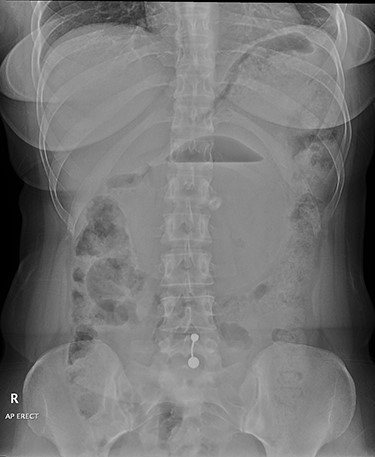

Anterior–posterior erect abdominal radiograph showing a large balloon seen in the middle of the abdomen with air/fluid level. No features of intestinal obstruction or perforation. No abnormal abdominal calcifications are noted.

A plain erect abdominal radiograph (Fig. 1) was done, and it showed a large rounded balloon with air fluid level seen in the middle of the abdomen. No features of intestinal obstruction or perforation.